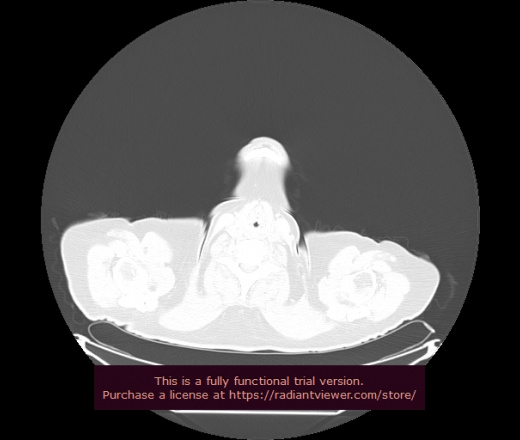

Уважаемые коллеги, если имеется интерес, сможете ли Вы спрогнозировать дальнейшее +-одинаковое течение процесса у 4 данных разных пациентов? Зацепиться где-то можно очень просто, где-то нельзя.